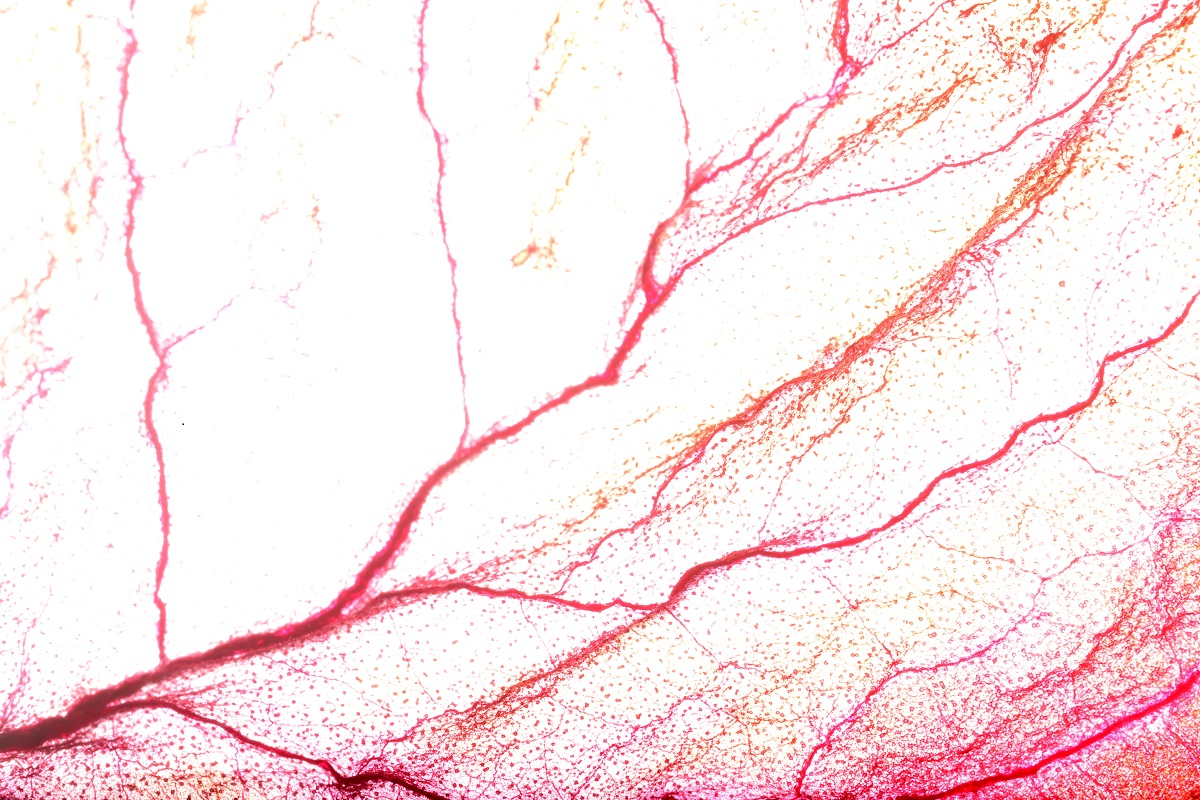

A health condition in which the walls of small arteries from the heart do not work correctly is known as small vessel disease. The body cannot get enough oxygen due to this condition. The most common symptoms include breathing problems, chest pain, and other heart disease symptoms.

However, clogging or narrowing of the blood vessels that supply the heart can happen not only in large arteries but also in tiny arteries in the heart. Sometimes, this disease is called coronary microvascular disease or microvascular endothelial dysfunction.

The small arteries in the heart do not dilate (relax) completely. As a result, the heart does not get enough oxygen. While the exact cause is not known, experts believe that small vessel disease is caused by the same conditions that lead to large vessel disease. For example hypertension, high cholesterol levels, obesity, and diabetes.